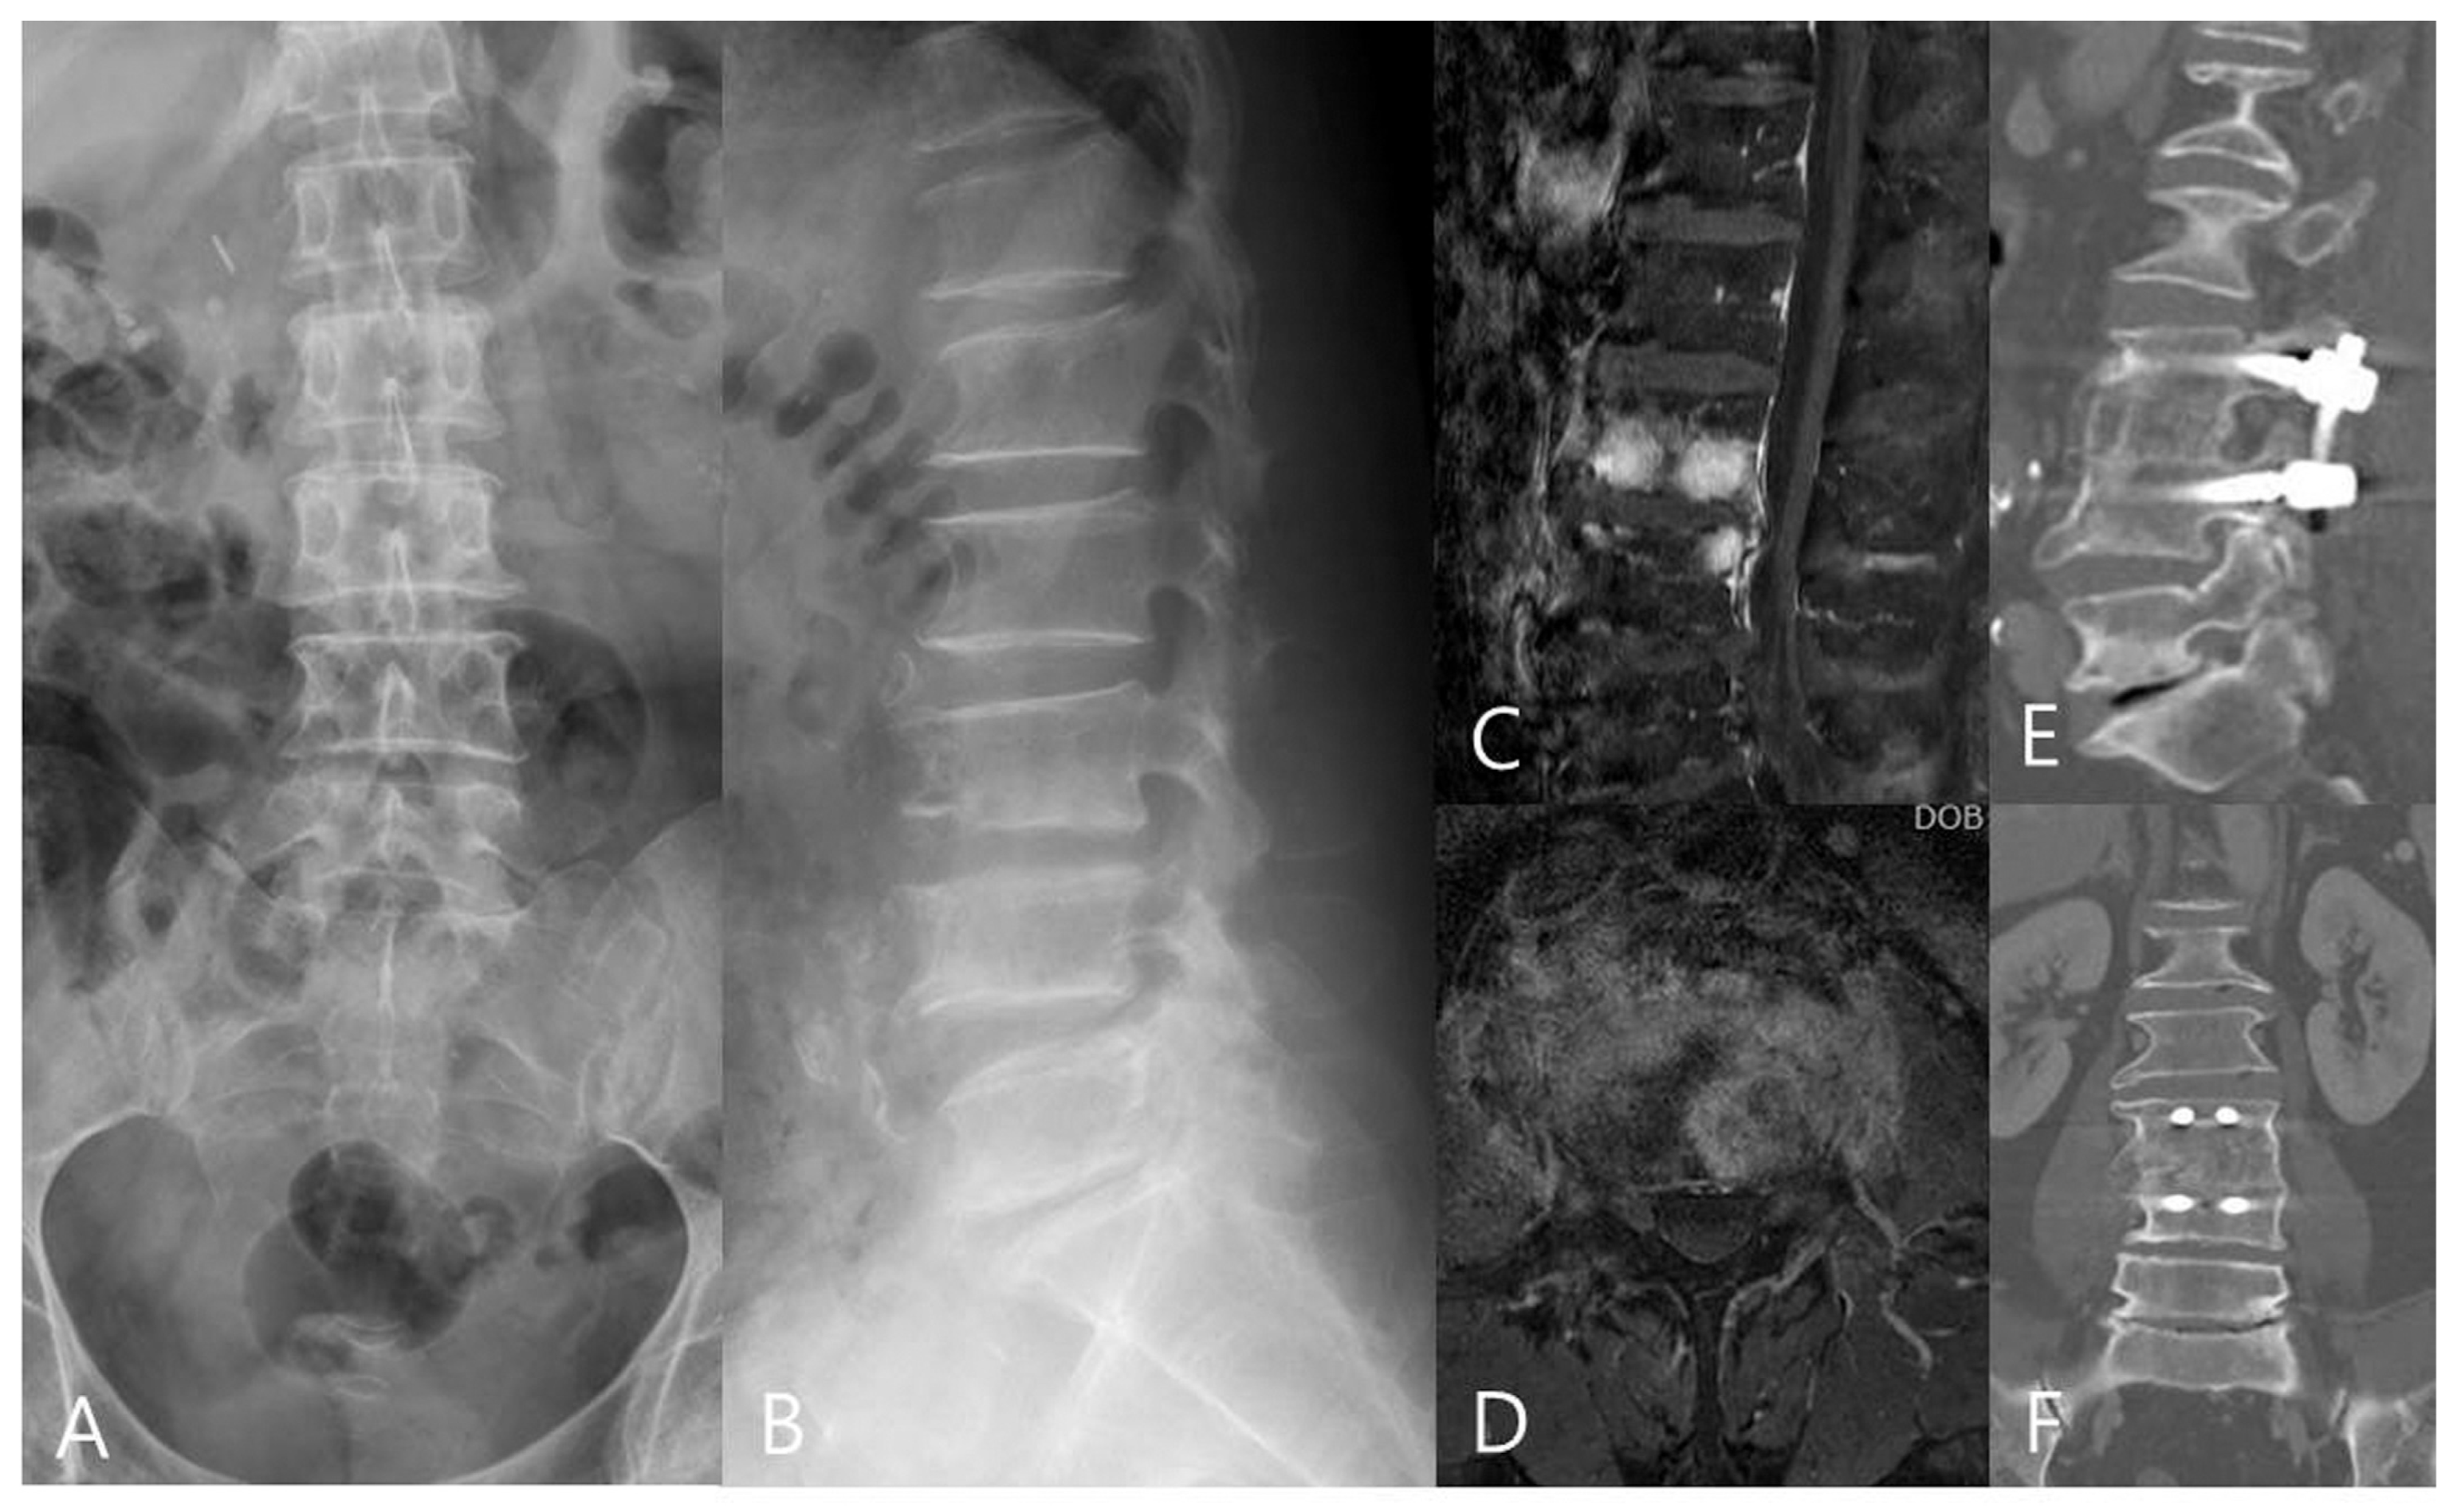

Figure 2.

A 53−year−old woman had lower back pain for more than 2 months. (A,B) The preoperative AP, lateral radiographs, and (C,D) MRI images revealed L3/4 pyogenic spondylodiscitis with endplate destruction. An anterior lumbar interbody fusion with a tri-cortical iliac bone graft was performed. (E,F) CT images at the last follow-up showed L3/4 interbody fusion and good sagittal alignment.

The intraobserver agreement rate was 96% (mean k = 0.83) and interobserver agreement rate was 93% (mean k = 0.77); good agreement was presented. The radiographic outcome measures are presented in Table 2. The pre-operative LL, RL, PI, and PT of both groups were similar. The postoperative and final follow-up LL, RL, and DH were improved in both groups (p < 0.001) (Figure 1 and Figure 2). The improvements of LL of both groups were not statistical different, but the improvement of RL and DH for the OLIF group was better than that found for the ALIF group (p < 0.001). At the final follow-up, although the LL and RL of both groups had decreased slightly, the data were not statistically significant for either group.